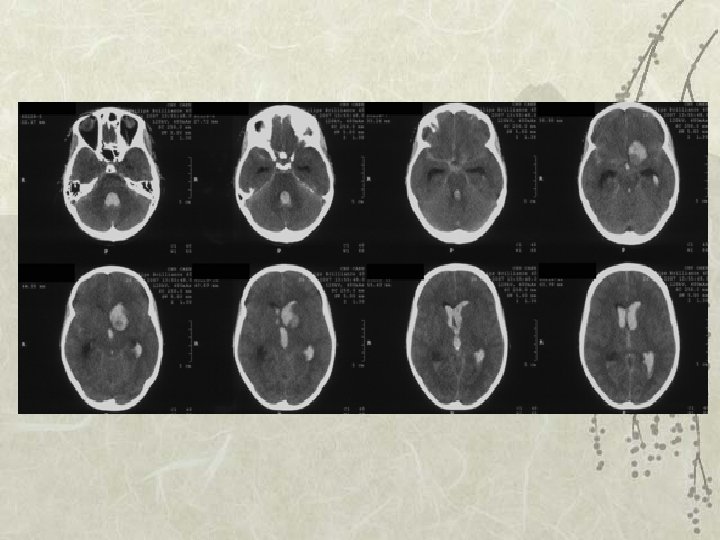

Cas clinique v v v SCANNER: Fischer 4 Hématome temporal gauche , HSD aigu Hémorragie intraventriculaire Prise en charge initiale: – Artériographie: deux anévrismes carotide gauche – Chirurgie pour évacuation de l’hématome et clip sur l’anévrisme

Récidive HSA à J 8 / Coma

J 1 post opératoire

Vasospasme de l’artère sylvienne à J 8 Se traduisant par un infarcissement sylvien profond et superficiel Avec effet de masse et engagement sous falcoriel